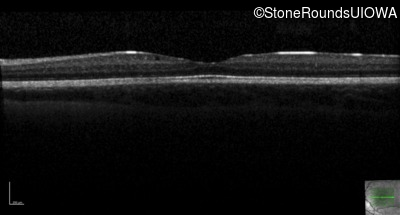

This 6 year old boy first experienced difficulty reading and seeing the blackboard at age 5.

| Age at visit: 6 years |

| Age at visit: 11 years |

| Age at visit: 14 years |

| Age at visit: 14 years (Visit 2) |